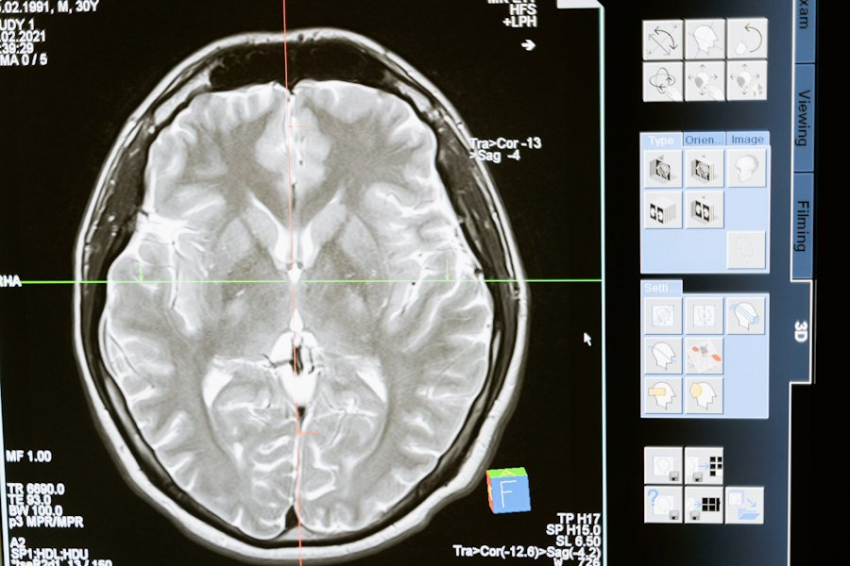

Фото из открытых источников Психологи из The Francis Crick Institute в Лондоне предложили методику лечения генетической формы эпилепсии, основанный на замене отсутствующего фермента, необходимого для нормального функционирования мозга, сообщается на портале Molecular Psychiatry (MP). Эпилепсия — это заболевание,...